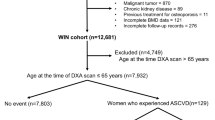

A total of 648 women were included in the current study, with a mean (SD) age of 79.7 (2.5) years at the baseline for this analysis. While 744 women had valid AAC and pQCT data at baseline, 94 women were excluded for bisphosphonate and/or warfarin use (n = 54 for bisphosphonates; n = 36 for warfarin; n = 4 for both), and another two women were excluded due to missing BMI data (Fig. 1). For longitudinal analyses, 551 women had valid data on AAC progression, while 645 women had valid pQCT bone change data from at least one bone site. There were no differences in demographic, AAC or pQCT bone measures between women with and without valid longitudinal AAC or bone data (data not shown). Characteristics of the final sample at baseline are presented in Table 1.

Participant flowchart showing how the study population was derived. For pQCT, participants were included if they had data available for at least one of the three scan sites. Therefore, the number of participants specified here for the longitudinal analysis differs from the number of participants actually included in the analysis for each individual bone measure